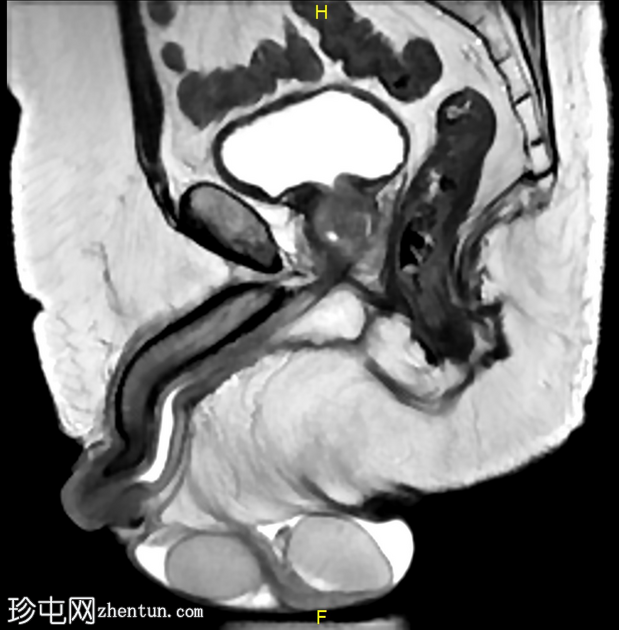

矢状位

T2加权像

龟头可见不规则形状的软组织肿块,增强后明显强化,并伴有扩散受限。该肿块侵犯尿道海绵体,导致远端尿道狭窄和上游尿道扩张。

左侧腹股沟可见多个肿大的病理性淋巴结,右侧可见较小的非特异性淋巴结。